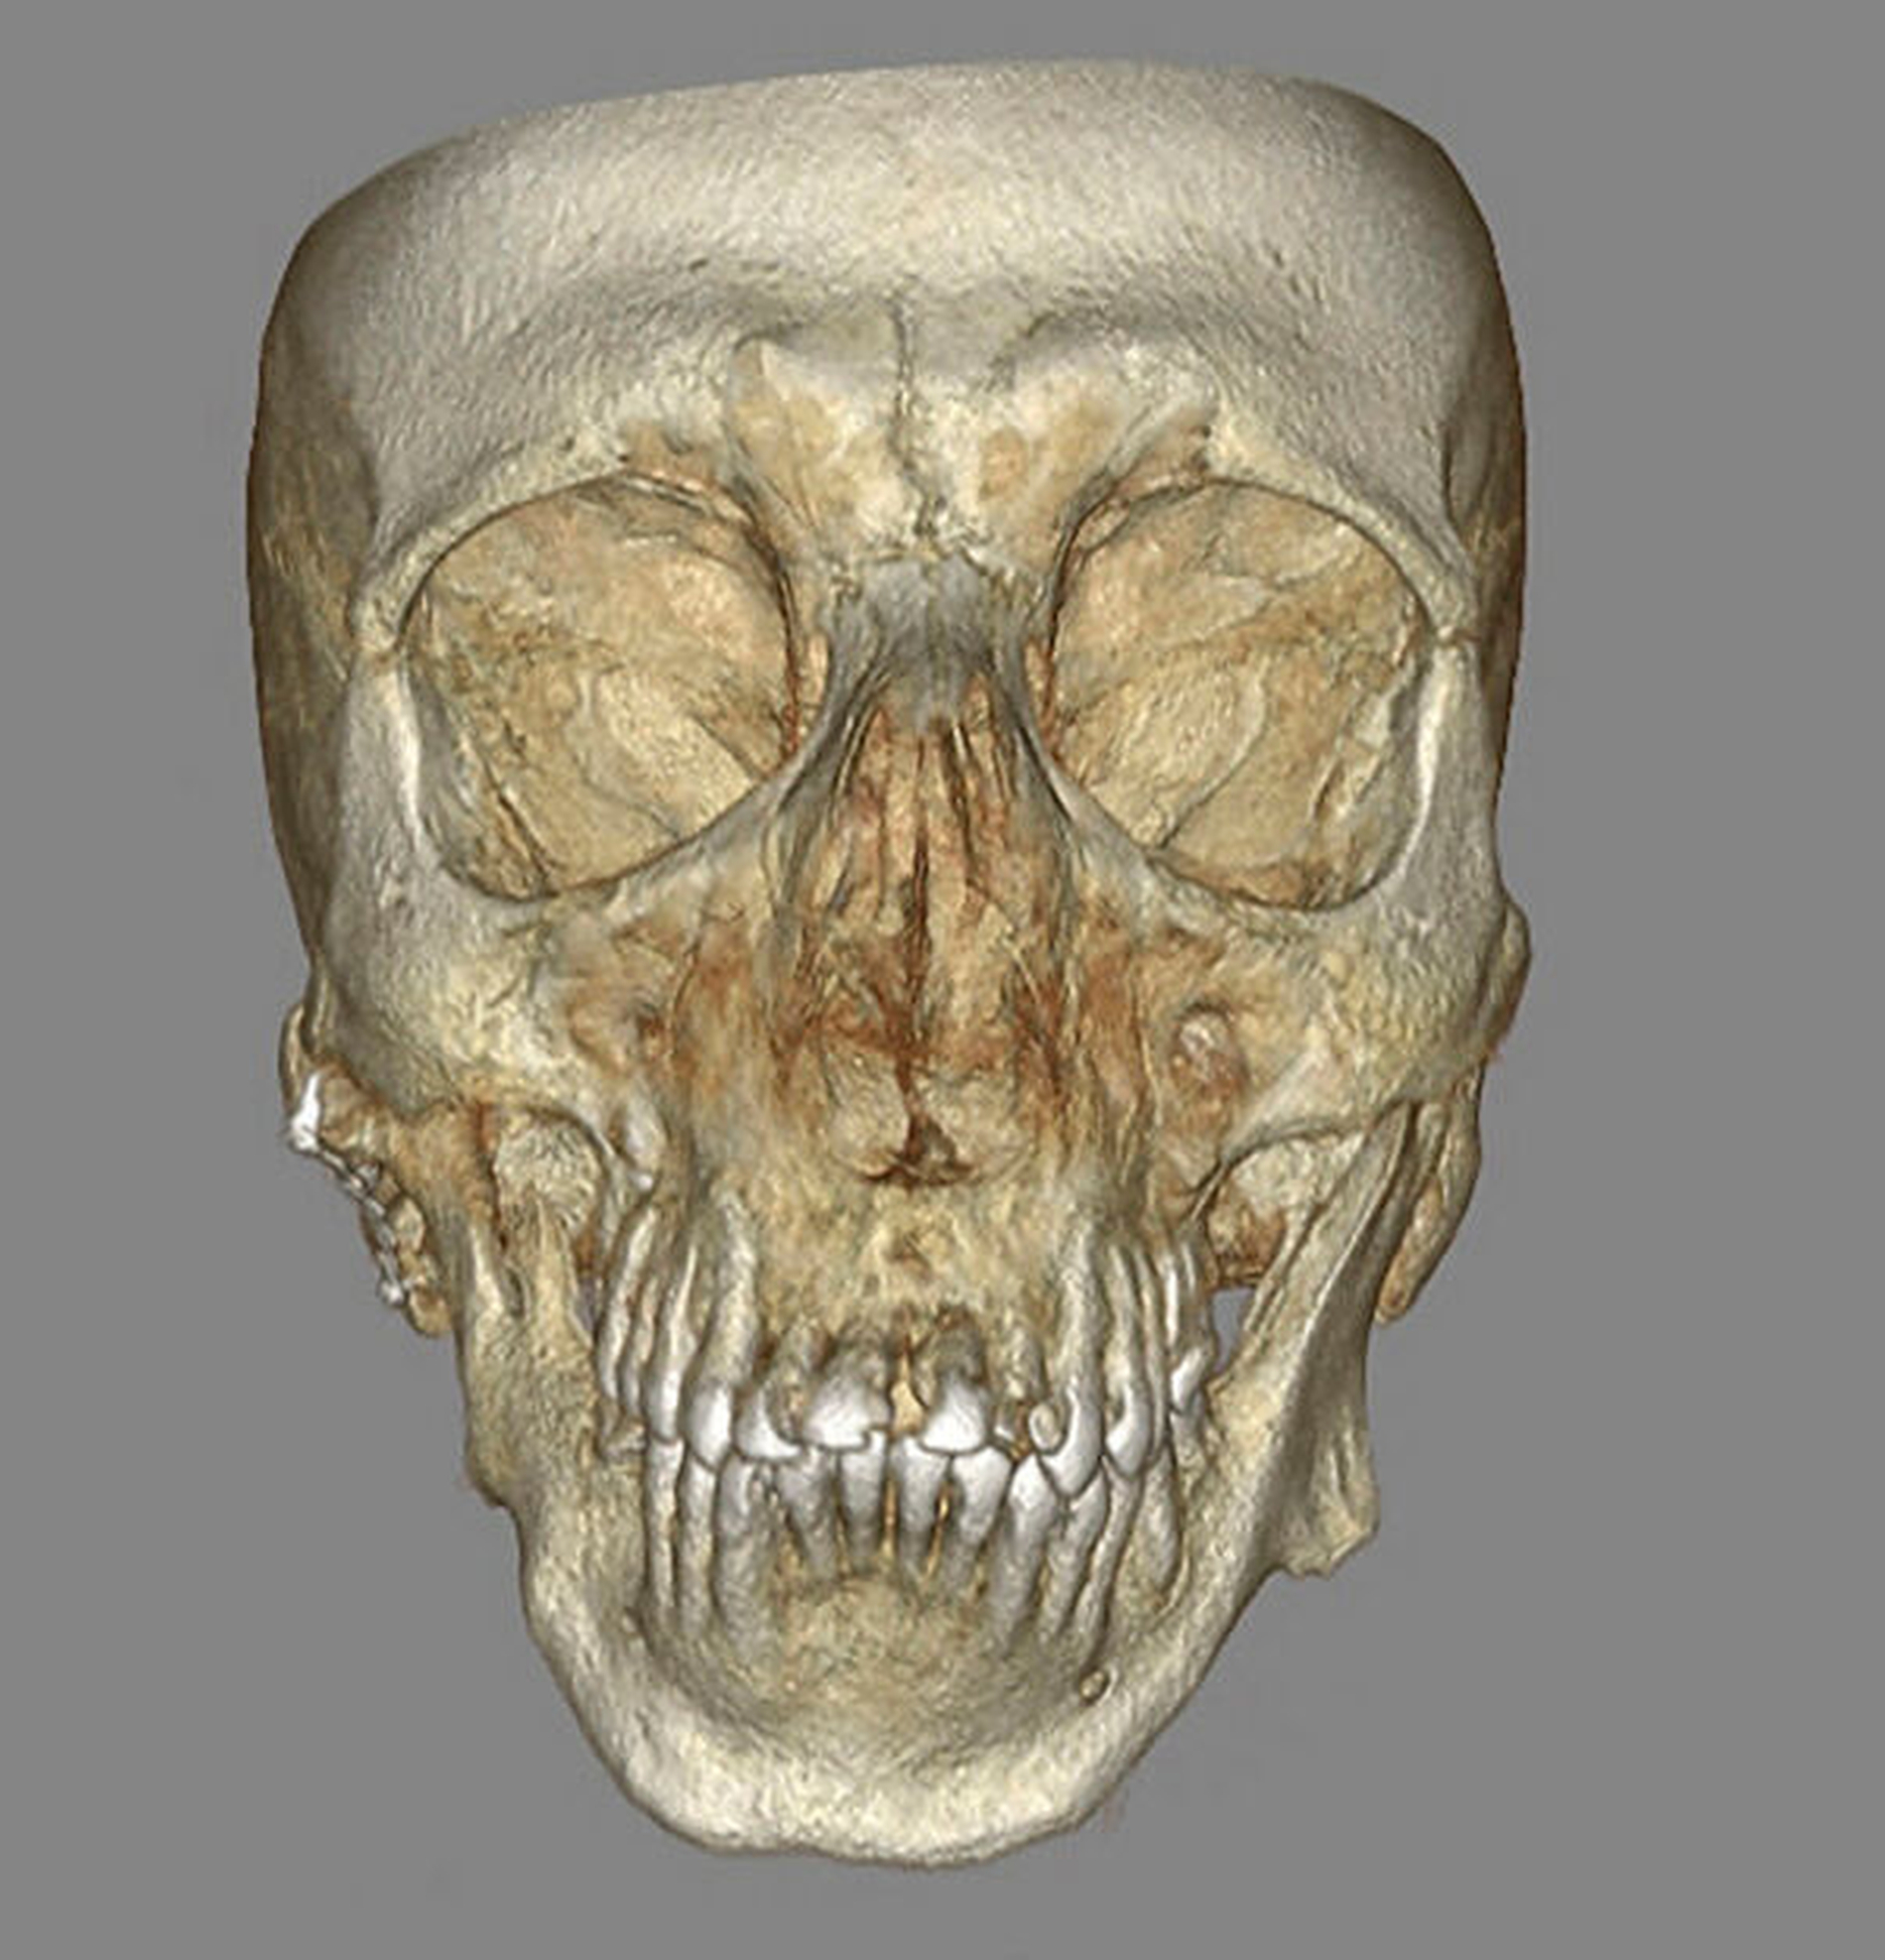

Aus der Krankengeschichte des Patienten ergab sich eine im Jahr 2009 durchgeführte Operation mit costochondralem Kiefergelenksersatz rechts aufgrund einer fortgeschrittenen Kiefergelenksarthrose infolge eines Sturzereignisses mit beidseitig unbehandelter Collumfraktur im Kindesalter. Eine noch am Tag der Erstvorstellung durchgeführte DVT-Untersuchung zur Beurteilung der Kiefergelenke bei ausgeprägter Unterkieferhypomobilität bestätigte die Verdachtsdiagnose einer Kiefergelenksankylose Typ IV rechts und Typ III links nach Sawhney [Sawhney, 1986] beziehungsweise Wilkes Typ V [Wilkes, 1989] beidseits (Abbildung 2).